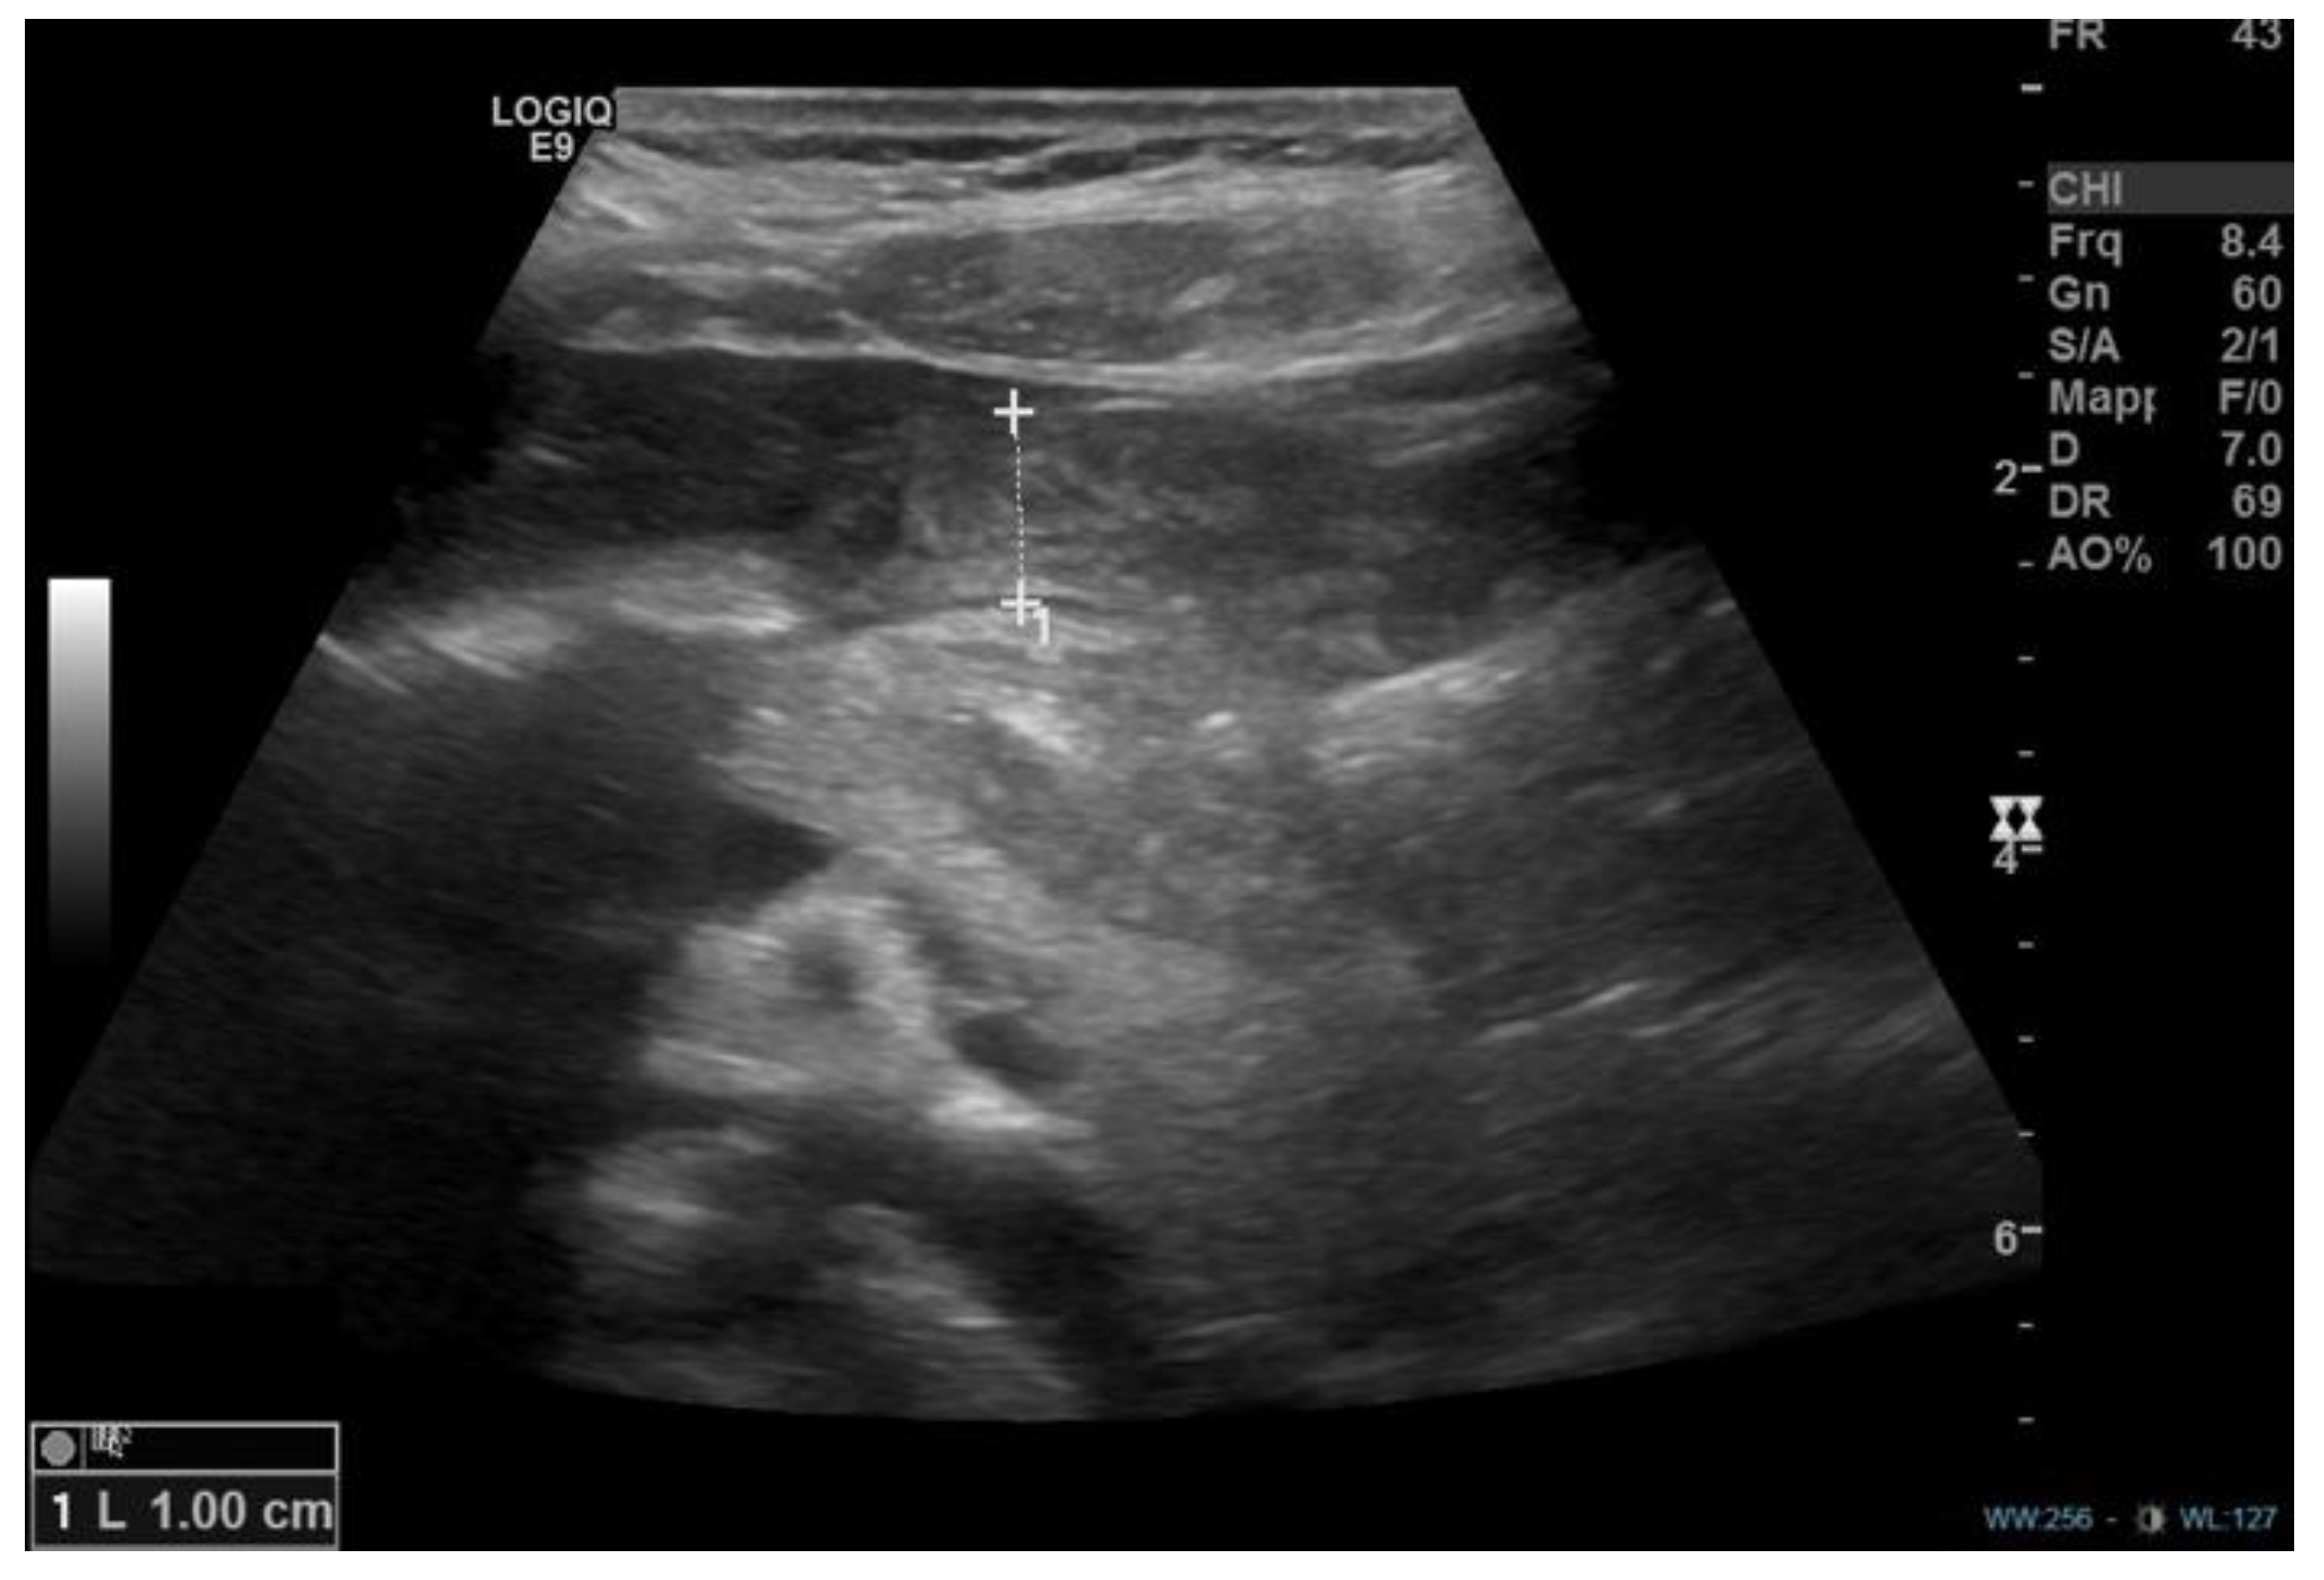

- Plessi, C.; Sica, M.; Molinaro, F.; Fusi, G.; Rossi, F.; Costantini, M.; Roviello, F.; Marano, L.; D’ignazio, A.; Spinelli, C.; et al. Diagnosis and treatment of primary hypertrophic pyloric stenosis (HPS) in older children. J. Pediatr. Surg. Case Rep. 2021, 69, 101860. [Google Scholar] [CrossRef]